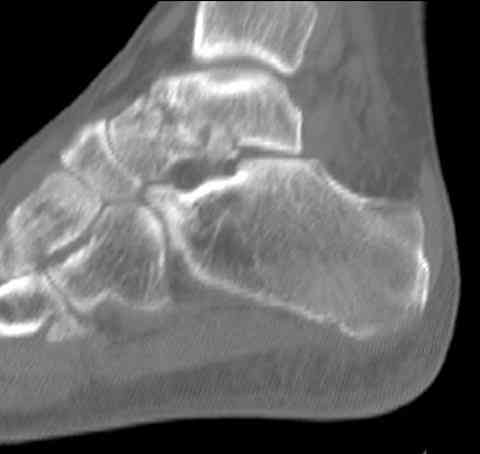

Случай с множественным оскольчатым переломом тарана оперированный из двойного доступа.

Через 2 мес.: